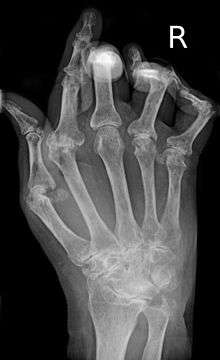

A hand affected by rheumatoid arthritis | |

Rheumatoid arthritis (RA) is a long-lasting autoimmune disorder that primarily affects joints. It typically results in warm, swollen, and painful joints. Pain and stiffness often worsen following rest. Most commonly, the wrist and hands are involved, with the same joints typically involved on both sides of the body. The disease may also affect other parts of the body. This may result in a low red blood cell count, inflammation around the lungs, and inflammation around the heart. Fever and low energy may also be present.[1] Often, symptoms come on gradually over weeks to months.[2]

Arthritis of joints involves inflammation of the synovial membrane. Joints become swollen, tender and warm, and stiffness limits their movement. With time, multiple joints are affected (polyarthritis). Most commonly involved are the small joints of the hands, feet and cervical spine, but larger joints like the shoulder and knee can also be involved.[11]:1089 Synovitis can lead to tethering of tissue with loss of movement and erosion of the joint surface causing deformity and loss of function.[2]

RA typically manifests with signs of inflammation, with the affected joints being swollen, warm, painful and stiff, particularly early in the morning on waking or following prolonged inactivity. Increased stiffness early in the morning is often a prominent feature of the disease and typically lasts for more than an hour. Gentle movements may relieve symptoms in early stages of the disease. These signs help distinguish rheumatoid from non-inflammatory problems of the joints, often referred to as osteoarthritis. In arthritis of non-inflammatory causes, signs of inflammation and early morning stiffness are less prominent with stiffness typically less than one hour, and movements induce pain caused by mechanical arthritis.[12] The pain associated with RA is induced at the site of inflammation and classified as nociceptive as opposed to neuropathic.[13] The joints are often affected in a fairly symmetrical fashion, although this is not specific, and the initial presentation may be asymmetrical.[11]:1089

As the pathology progresses the inflammatory activity leads to tendon tethering and erosion and destruction of the joint surface, which impairs range of movement and leads to deformity. The fingers may suffer from almost any deformity depending on which joints are most involved. Specific deformities, which also occur in osteoarthritis, include ulnar deviation, boutonniere deformity (also "buttonhole deformity", flexion of proximal interphalangeal joint and extension of distal interphalangeal joint), swan neck deformity (hyperextension at proximal interphalangeal joint and flexion at distal interphalangeal joint) and "Z-thumb." "Z-thumb" or "Z-deformity" consists of hyperextension of the interphalangeal joint, fixed flexion and subluxation of the metacarpophalangeal joint and gives a "Z" appearance to the thumb.[11]:1089 The hammer toe deformity may be seen. In the worst case, joints are known as arthritis mutilans due to the mutilating nature of the deformities.[14] "Spindling of fingers" of hand occurs due to swelling of the PIP but not DIP joints. "Piano key movement" of the ulnar styloid occurs due to inflammation around the ulnar styloid and tenosynovitis of extensor carpi ulnaris.

X-rays of the hands and feet are generally performed in people with many joints affected. In RA, there may be no changes in the early stages of the disease or the x-ray may demonstrate juxta-articular osteopenia, soft tissue swelling, and loss of joint space. As the disease advances, there may be bony erosions and subluxation. X-rays of other joints may be taken if symptoms of pain or swelling occur in those joints.